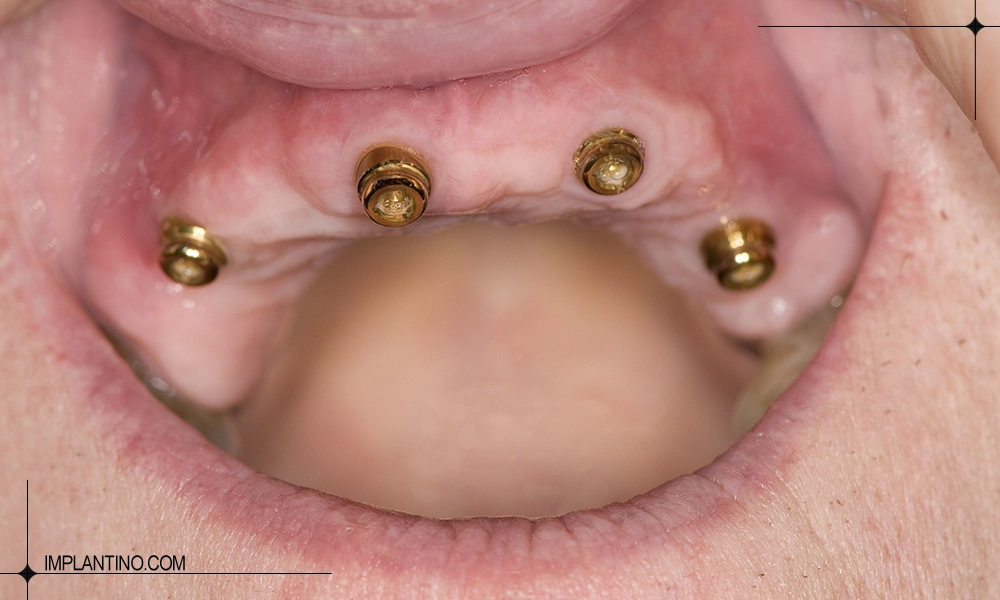

- فک پایین: به دلیل تراکم بالاتر استخوان، معمولاً بین ۴ تا ۵ ایمپلنت برای پوشش کامل فک کافی است.

- برای فک پایین: ۴ تا ۵ ایمپلنت به طور معمول نیاز است.

تعداد ایمپلنت برای فک پایین

برای فک پایین، به دلیل تراکم بالاتر استخوان، معمولاً بین ۴ تا ۵ ایمپلنت برای جایگزینی کامل دندان ها کافی است. فک پایین استحکام بیشتری دارد و ایمپلنت ها در این فک فشار جویدن را بهتر تحمل می کنند، بنابراین نیاز به تعداد بیشتر نخواهد بود. با این حال، تعداد دقیق ایمپلنت برای هر بیمار بر اساس معاینات دندانپزشکی، اسکن سه بعدی و وضعیت لثه تعیین می شود تا ثبات و دوام پروتز بهینه شود.